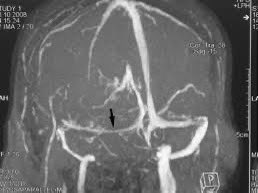

- MRI imaging to exclude tumor, venous sinus thrombus, and other structural causes of intracranial hypertension